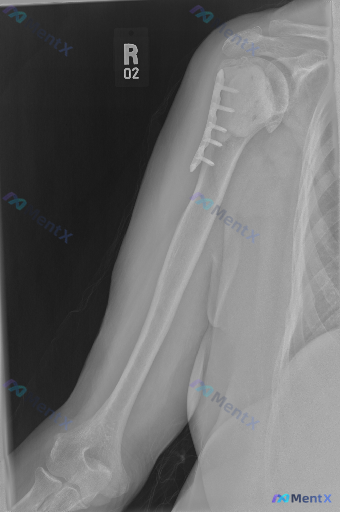

这张右肩及上臂正位X光片,除了术后改变之外,还需要警惕哪些异常?

整理到一张右肩部及上臂正位X光片的资料,来自一位肱骨近端骨折术后复查的患者。

影像上能看到:右肱骨近端外侧有金属接骨板和数枚螺钉固定,螺钉位置在骨骼内,未见明显金属断裂或松动;骨折断端(推测外科颈附近)有连续骨痂形成,骨小梁有跨越迹象,皮质连续性良好,未见新发骨折线;盂肱关节、肩锁关节对位尚可,关节间隙未见明显异常;骨质密度较均匀,除内固定外未见明显异常透亮或高密度影;周围软组织影未见明显肿胀或异常钙化,除内固定外未见其他异物。

想和大家讨论一下:除了明确的术后改变之外,这张影像还可能存在哪些需要警惕的异常?单看目前这组资料,你会优先把方向放在哪边?